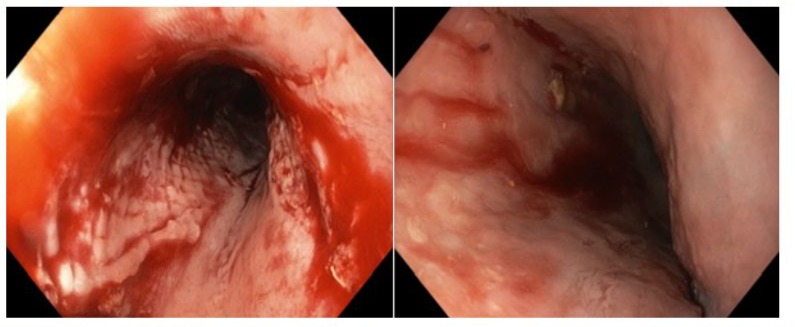

We present the case of a 66-year-old male with Spontaneous Oesophageal Perforation treated with Oesophageal Stenting. This patient reports sudden onset severe anterior chest pain after coughing and haematemesis. He has a background medical history of Type II Diabetes Mellitus, End Stage Renal Failure on Haemodialysis, Hypertension, Obstructive Sleep Apnoea and takes prophylactic Aspirin. Computed Tomography demonstrated pneumomediastinum with contamination (Figure 1). Endoscopic investigation was undertaken. This revealed multiple areas of oesophageal perforation including mucosal tears in the proximal, middle, and distal oesophagus of varying size as well as a haematoma extending the entire length of the oesophagus to the cardio-oesophageal junction (Figure 2). This endoscopy was abandoned due to respiratory compromise secondary to bilateral pneumothoraxes requiring immediate decompression with bilateral chest drains. The patient was not suitable for an oesophagectomy due to their multiple comorbidities and physiological status. The decision was made to use a WallFlex™ Fully Covered Oesophageal Stent (Boston Scientific, Mascot, NSW Australia). This stent was removed three weeks later, and gastroscopy revealed re-epithelialisation of the entire oesophagus along with complete resolution of the perforation at the mid-oesophagus (Figure 3). The patient’s dysphagia continued to improve, and his diet was progressed and discharged home.

Figure 2: Endoscopic image demonstrating a) extensive oesophageal haematoma and b) multiple full thickness perforations.